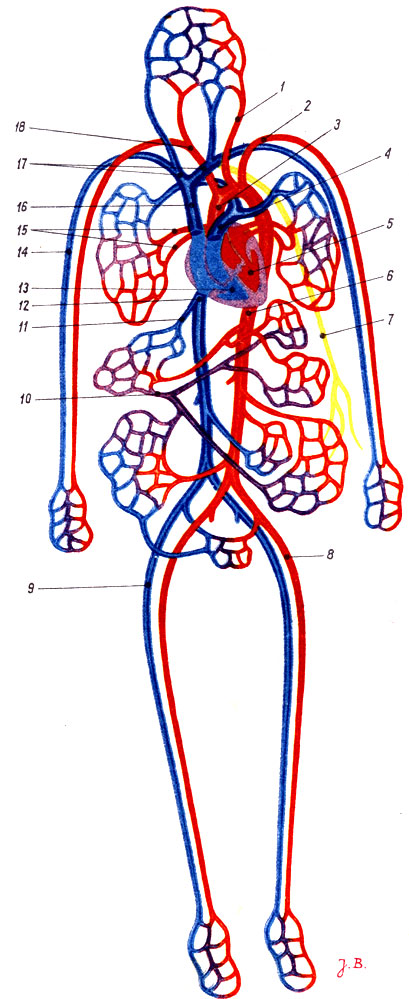

Кровеносная система человека: структура и функции